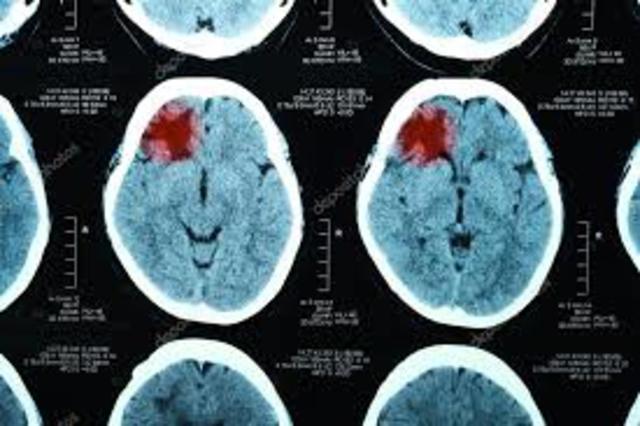

• IMAGENES CRANEALES

IMAGENES CRANEALES

En 1971 se instala en EEUU el primer equipo de tomografía computarizada especializado en

imágenes craneales.